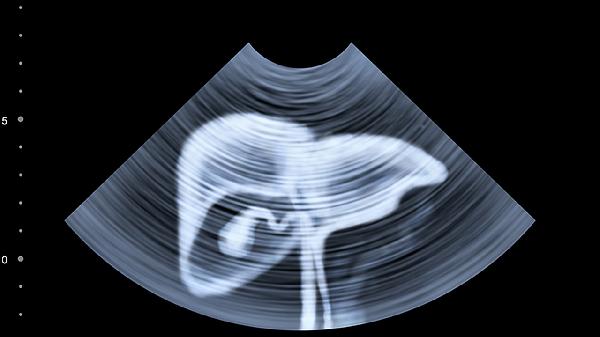

甲胎蛋白偏高通常建议做肝脏B超检查。甲胎蛋白升高可能与肝炎、肝硬化、肝癌等肝脏疾病有关,肝脏B超有助于明确病因。

甲胎蛋白是一种糖蛋白,主要由胎儿肝细胞和卵黄囊合成,出生后水平迅速下降。成人甲胎蛋白升高常见于肝脏疾病,如慢性肝炎活动期、肝硬化代偿期,此时肝细胞再生可能导致甲胎蛋白轻度升高。肝脏B超可以观察肝脏形态、结构变化,发现肝硬化结节、肝内占位性病变等异常。对于肝癌高危人群,如慢性乙肝病毒携带者、肝硬化患者,甲胎蛋白升高合并肝脏B超检查能提高早期肝癌检出率。部分非肝脏疾病如睾丸癌、卵巢癌也可能导致甲胎蛋白升高,但通常伴有其他特异性表现。

发现甲胎蛋白偏高应及时就医,在医生指导下完善肝脏B超、CT或MRI等检查。平时应注意避免饮酒、规律作息,慢性肝病患者需定期复查肝功能、病毒载量等指标。高危人群建议每6个月进行一次肝脏超声和甲胎蛋白联合筛查。